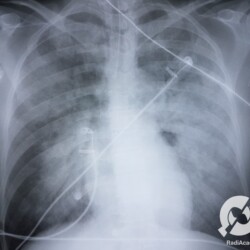

Consolidações alveolares difusas com predomínio peri-hilar, em “asa de borboleta”. Edema agudo de pulmão.